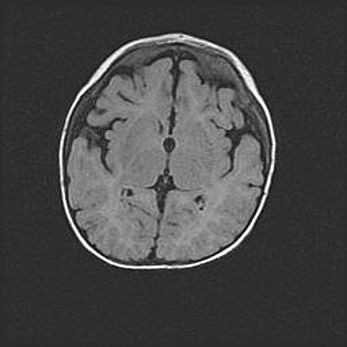

Церебральная ишемия II.

Возраст: 5 дней

Вес: 3400 г

Пол: женский

Окружность головы: 35 см

Срок гестации: 39 недель

Церебральная ишемия – это заболевание, характеризующееся недостаточностью (гипоксией) либо полным прекращением (аноксией) снабжения мозга кислородом по причине закупорки одного или нескольких сосудов. Это приводит к  что метаболическим расстройствам различной степени тяжести в тканях головного мозга, развитию коагуляционных некрозов и гибели нейронов.